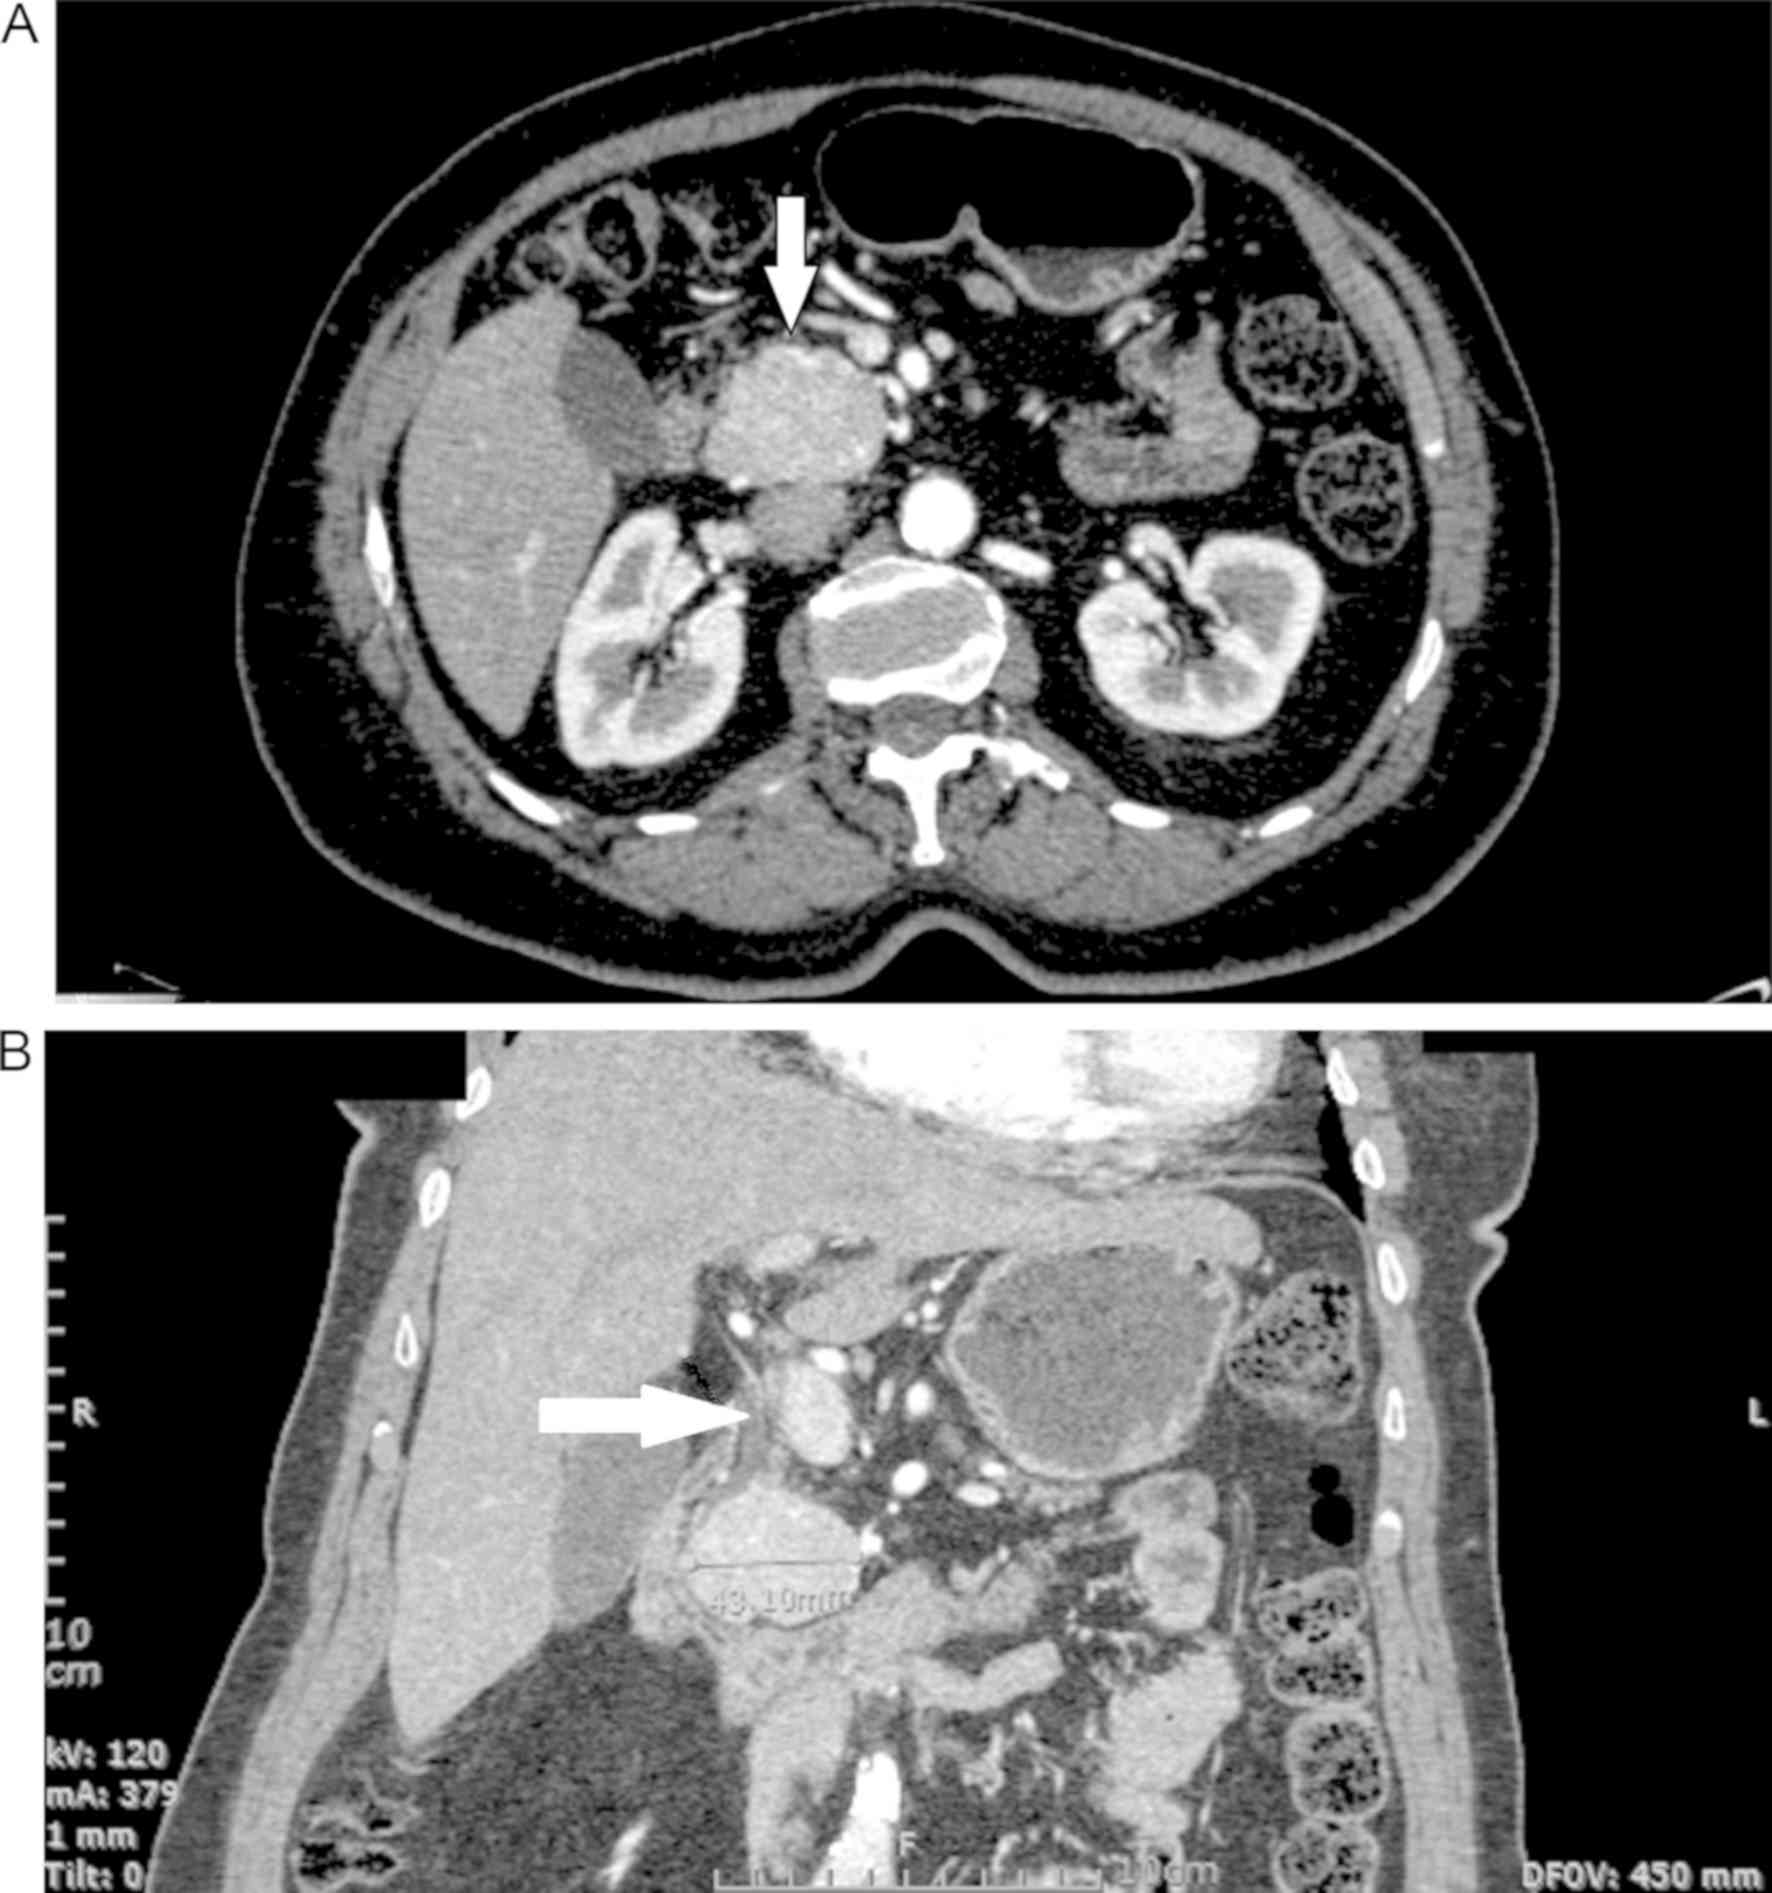

Insulinomas are rare tumors of the islet cells of the pancreas and are the most common cause of endogenous hyperinsulinism. Although they usually present with symptoms of hypoglycemia, sometimes they can have vague symptoms. We present the case of a 62‑year‑old diabetic female who was diagnosed with a large insulinoma after being investigated for the ‘cure’ of her diabetes. We also review the literature regarding insulinomas in patients with diabetic. A 62‑year‑old, obese woman with type 2 diabetes mellitus was initially investigated for an unexplained normalization of her blood glucose levels after the cessation of antidiabetic medication due to an episode of severe hypoglycemia. She remained without antidiabetics for three months maintaining normoglycemia, and thereafter, she started experiencing frequent but less severe hypoglycemic episodes. She did not change her diet habits or level of activity and did not lose any weight. The patient underwent further investigation with a supervised 72 h fasting test, which resulted in the biochemical diagnosis of endogenous hyperinsulinism. Imaging studies revealed the presence of a large insulinoma in the head of the pancreas. Finally, the patient underwent a pylorus preserving Whipple procedure, which reversed the aforementioned ‘normalization’ of glucose levels and the underlying diabetes mellitus reappeared. Insulinomas are rare tumors causing hypoglycemia. Even more rarely are found in diabetic patients, making the diagnosis more challenging and probably delayed, as the symptoms are masked by the presence of diabetes, thereby leading to a more advanced disease diagnosis.

Figure 1